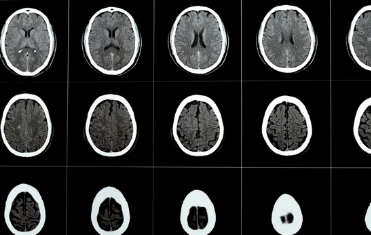

- 영상 검사: 뇌 CT, MRI, MRA 등 영상 검사를 통해 뇌혈관 막힘 여부와 위치, 뇌 손상 정도를 확인합니다.